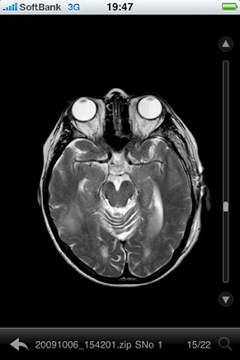

図2 iPhoneで表示した高精細のMR画像

1点目はいつ,どこにいても即時に質の高い正確な画像診断が可能になったことである。それは,iPhoneで閲覧できる画質のレベルが,画像診断が専門である放射線科専門医から見ても,院内での画像診断とほぼ同等の画像診断できるほどのレベルである(図2)。その高い画質レベルであるため,通常見落とされやすい少量のくも膜下出血でも十分診断可能である。また,iPhoneであるため詳細に見たい部分の拡大やウインドウレベルの調整も簡単に画面に触れるだけで変更可能である(図3a,b)。